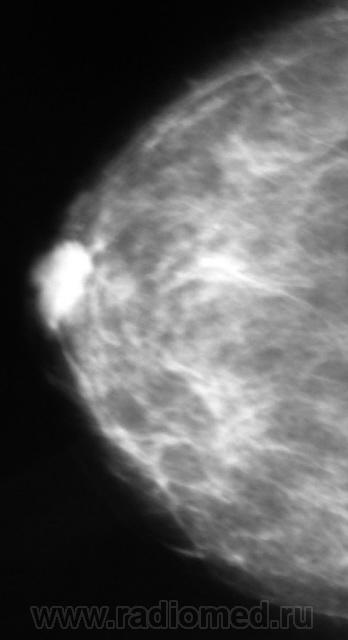

Ещё одна интересная маммография

Жалоб пациентка не предъявляет, просто иногда ощущает дискомфорт в мол.железах.

Кистозный ФАМ с одной стороны просто ФАМ с другой (где право-лево не указано на снимках)

Где прямые, где косые? Вероятно кисты, но могут быть и фиброаденомы, надо УЗИ и при кистах - пункционное удаление содержимого, при фиброаденомах - секторальная резекция.

А, мне, что-то больше симпатично, как "фиброаденомы".

Гадать кисты это или фиброаденомы без УЗИ - дело не благодарное, почему кисты ставлю на первое место потому, что чаще кисты бывают множественными.